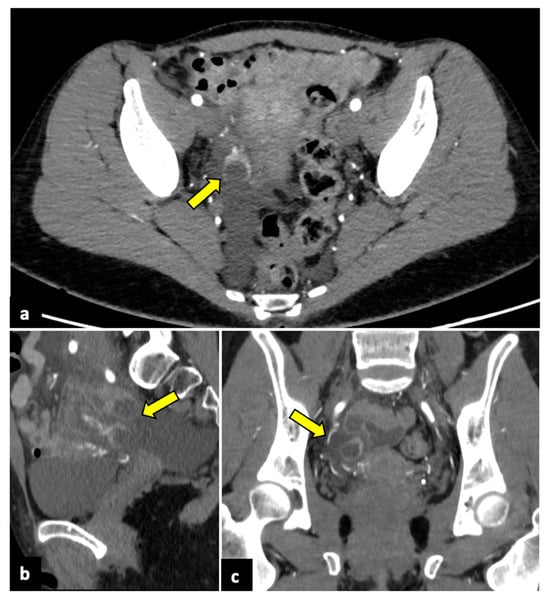

Pelvic malignancies, most commonly ovarian, cervical, and endometrial uterine cancers, can induce pain of different intensities and durations. Gynaecological cancer may present with sudden onset in cases of advanced stages, with the invasion of adjacent structures that lead to several complications, such as intestinal perforation, thrombosis, and intestinal or ureteral obstruction (Figure 10) [71,72,73].

Figure 10.

Advanced uterine cervical cancer in a 58-year-old subject attending the emergency department for abdominal pain and haematuria. CT axial (a), sagittal (b), and coronal (c) non-contrast images reveal the presence of a pelvic mass (blue arrows) and ureter causing ureteral obstruction (yellow arrows). The patient further underwent an MRI examination (d–f), which demonstrated a cervical tumour (blue arrows) invading the parametrium and ureters bilaterally (yellow arrows), the vagina, and the bladder. The uterine cavity was also obstructed and dilatated (red arrows).